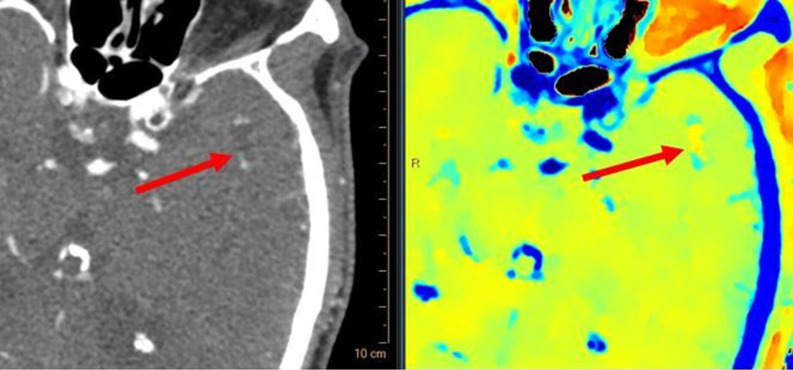

Teaching point: Spectral tomography offers valuable complementary diagnostic tools in the setting of cerebral fat macroembolism, a rare condition often presenting with nonspecific clinical symptoms.

Abstract Image